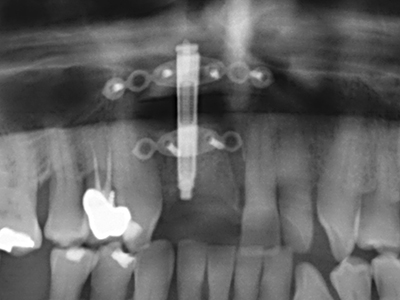

When surgical procedures are performed on bone in the immediate vicinity of sensitive structures such as blood vessels or nerves, rotary instruments pose a significant risk of iatrogenic injury. Piezoelectric devices can be helpful for preparation of bone covers and removal of hard tissue close to nerves, particularly for exposure of nerves after iatrogenic injury but also during nerve lateralization for resective and reconstructive procedures or implant placement (Fig. 17-20). Light contact between the piezotip and the nerve does not generally result in damage but proceeding incautiously with saw-like motions or attachments where a residual bone substrate remains may cause temporary or even permanent nerve damage. However, the risk of damage is considered to be substantially lower than when using saws or milling instruments (Pereira, Gealh et al. 2014).